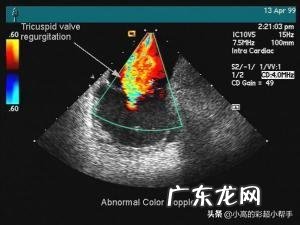

【B超和彩超有什么区别?】彩超是利用多普勒效应来增加了对运动组织的检查,特别是血流信号等 。